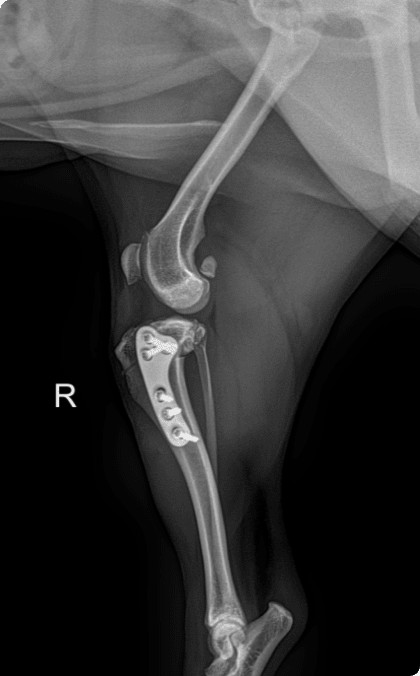

십자인대 단열은 정교한 외과 수술이 핵심입니다.

TTA/TPLO 등을 포함한 다양한 수술 옵션으로 환자 맞춤 치료를 제공합니다.

전방십자인대는 무릎 관절의 안정성을 유지하는 구조물로

외상이나 반복적 손상으로 단열될 수 있음.

약물치료만으로는 회복이 어렵고 수술적 교정이 필요함.